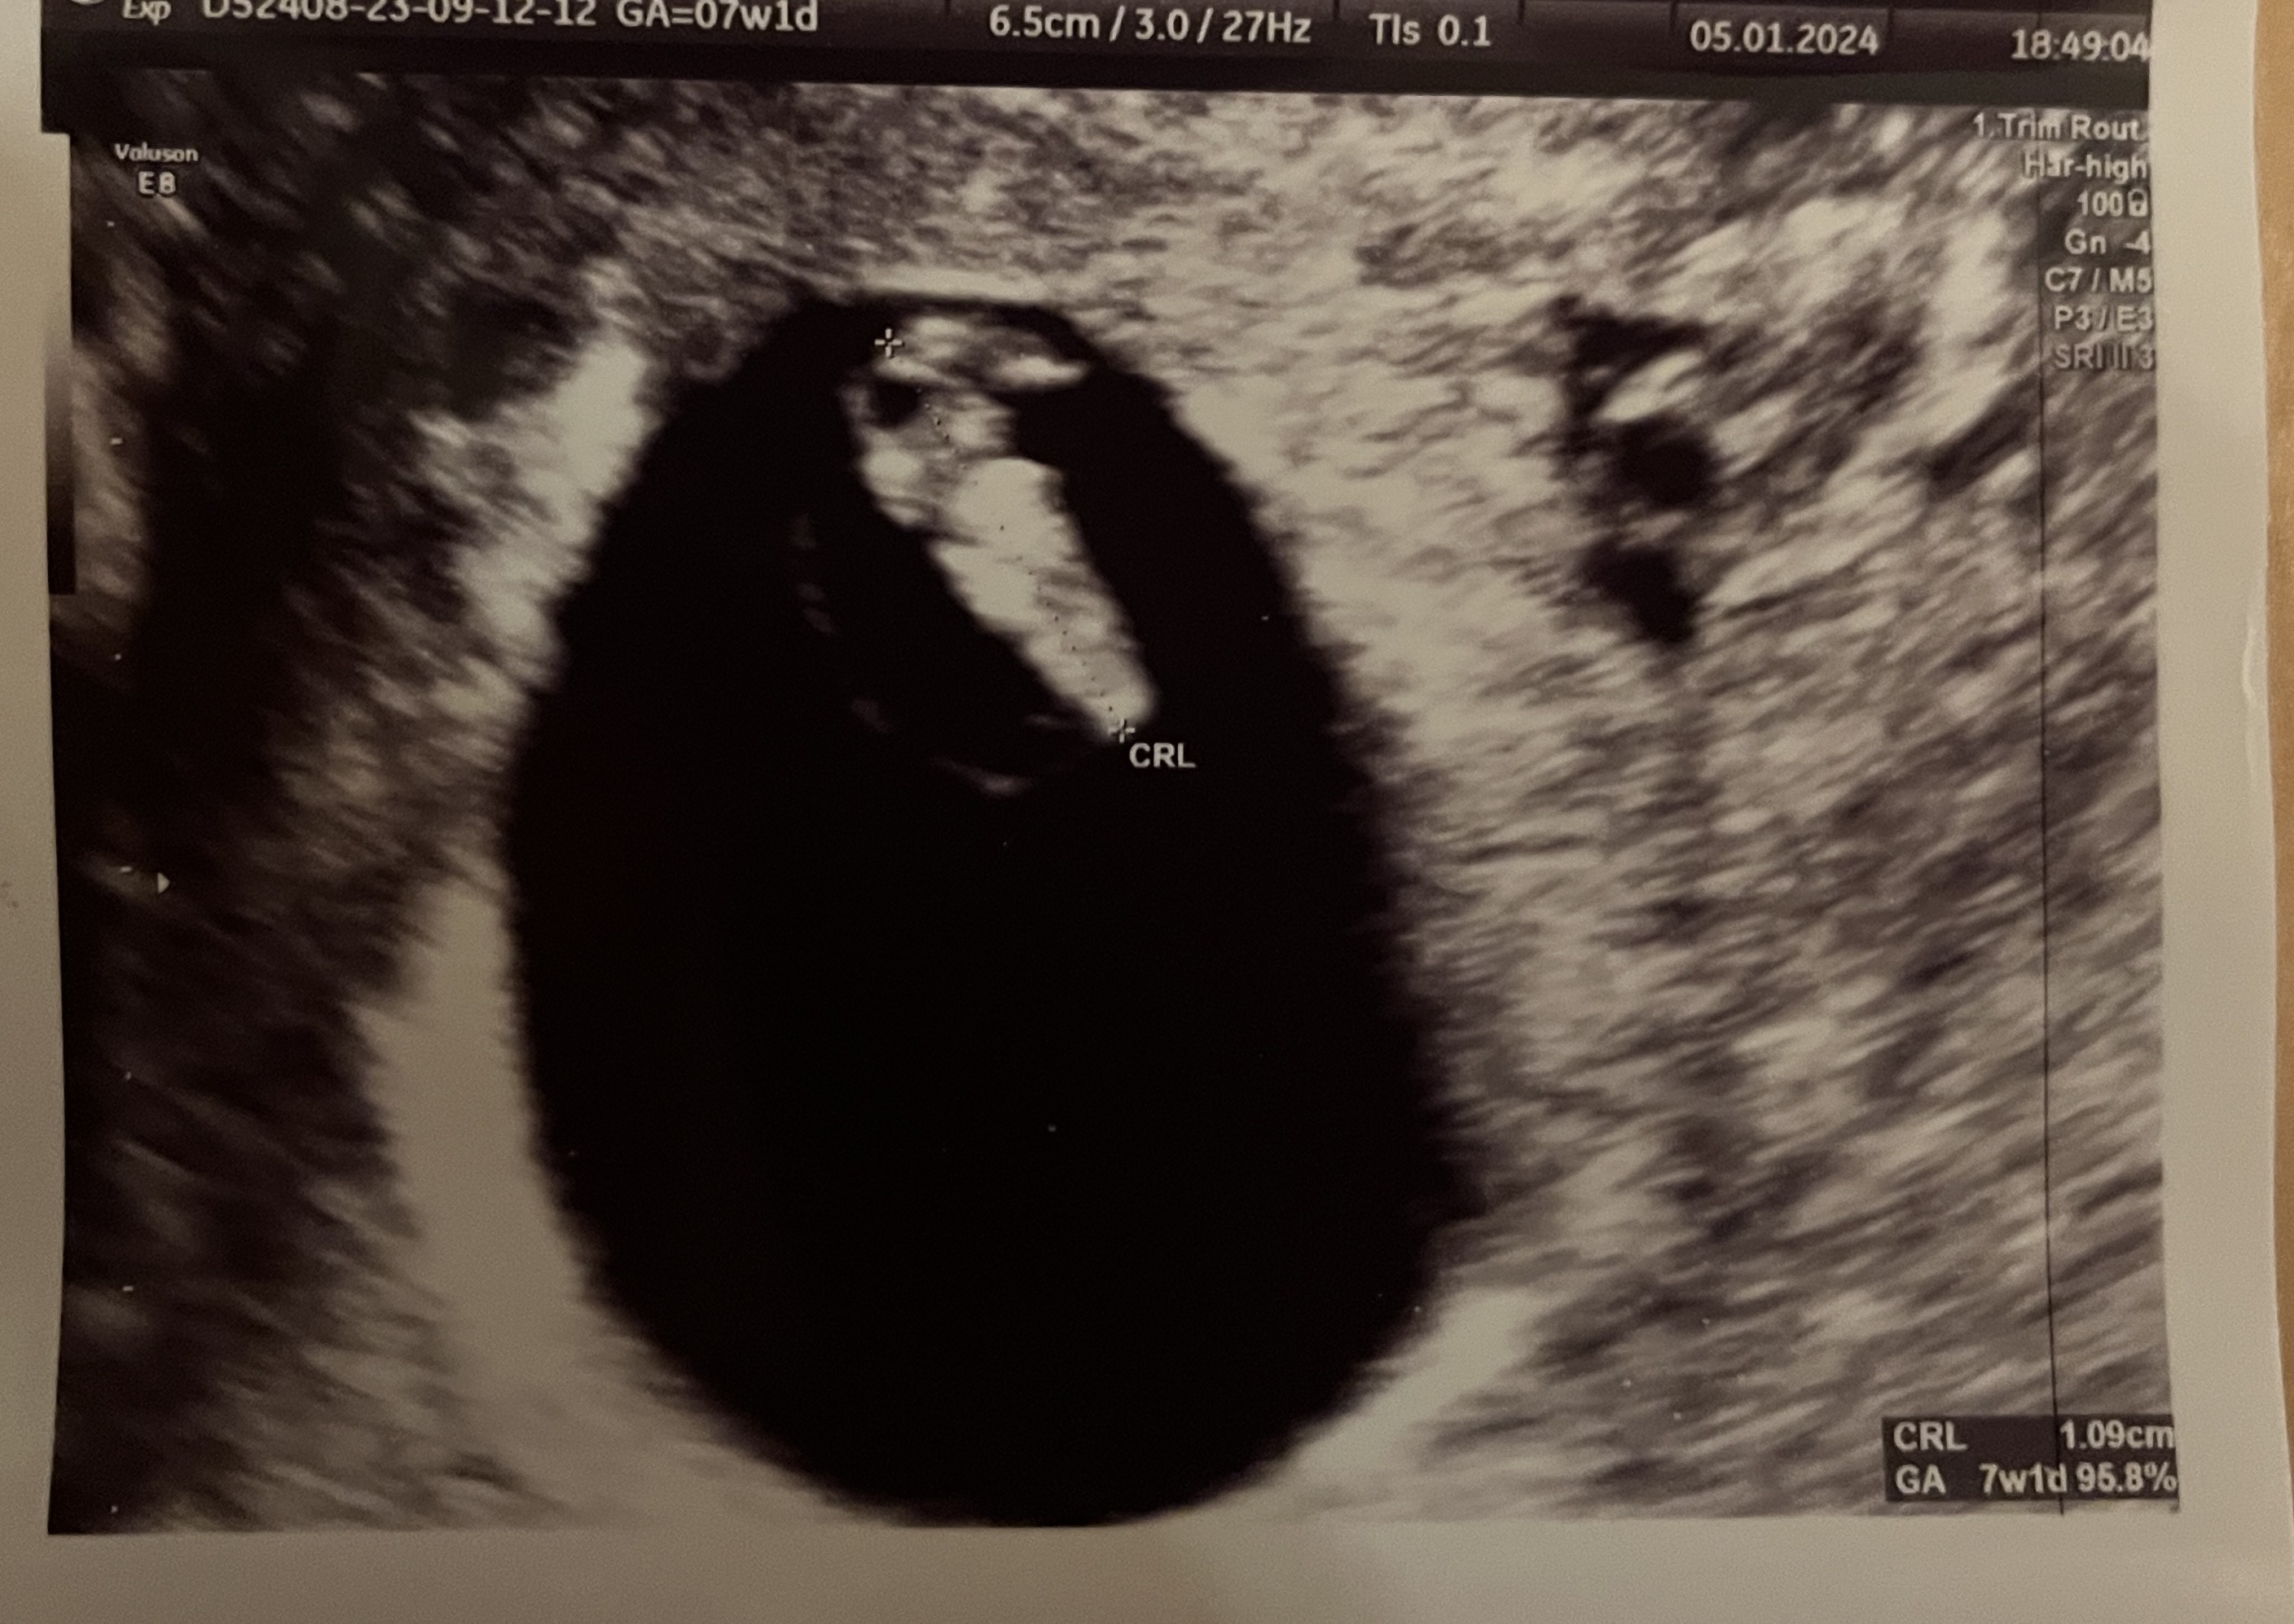

Dziewczyny może trochę w bardziej optymistycznym temacie - ja już po wizycie i wszystko cacy 😌 Wiek z OM idealnie zgrał się z USG, 1,1 cm okrucha z serduchem ♥️ Nie mierzył tętna (z wiadomych względów), ale było widać jak ładnie szybko miga 🥰 Trochę bardziej optymistycznie patrzę w przyszłość i zaczynam wierzyć, że tym razem może będzie dobrze ☺️

Załączniki

• IMG_8195.jpeg

IMG_8195.jpeg

925,3 KB · Wyświetleń: 104